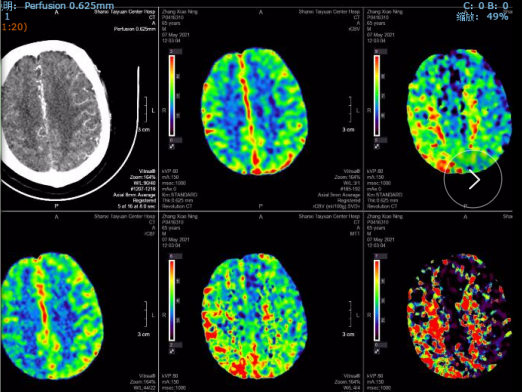

CTP:

右侧大脑半球均存在不同程度的低灌注区域。

此患者临床症状非急性右侧大脑中动脉闭塞患者,有左侧肢体偏瘫、语言不流利等较重的临床症状,NIHSS评分15分(意识提问2+凝视2+构音障碍1+面瘫1+偏瘫8+感觉障碍1),mRs评分4分,生活不能自理。但是头颅CT表现却不是整个右侧半球的大面积梗死,MRA和CTA均提示右侧大脑中动脉M1段闭塞,脑灌注提示右侧半球明显低灌注。提示虽然右侧大脑中动脉闭塞,但是其支配区域仍然有一定体积的处于低灌注目前尚未完全坏死的脑组织,符合血管内再通手术指征。